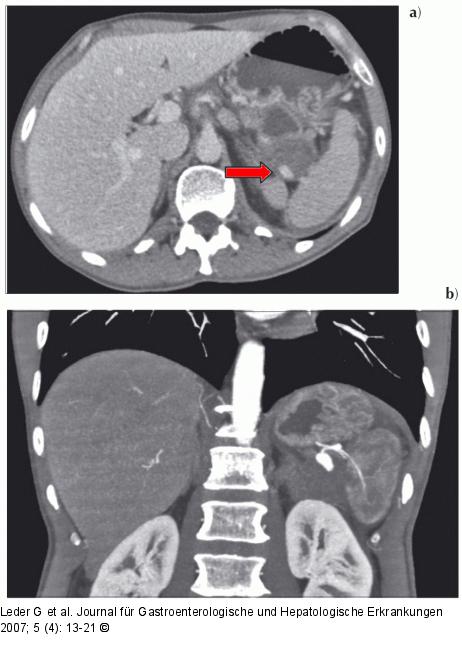

Abbildung 6: Chronische Pankreatitis a) Pankreaspseudozysten mit Milzarterienaneurysma (→). b) Die Gefäßrekonstruktion zeigt das Pseudoaneurysma noch deutlicher sowie die distal davon nur schmächtige A. lienalis. |

Abbildung 6: Chronische Pankreatitis

a) Pankreaspseudozysten mit Milzarterienaneurysma (→). b) Die Gefäßrekonstruktion zeigt das Pseudoaneurysma noch deutlicher sowie die distal davon nur schmächtige A. lienalis. |